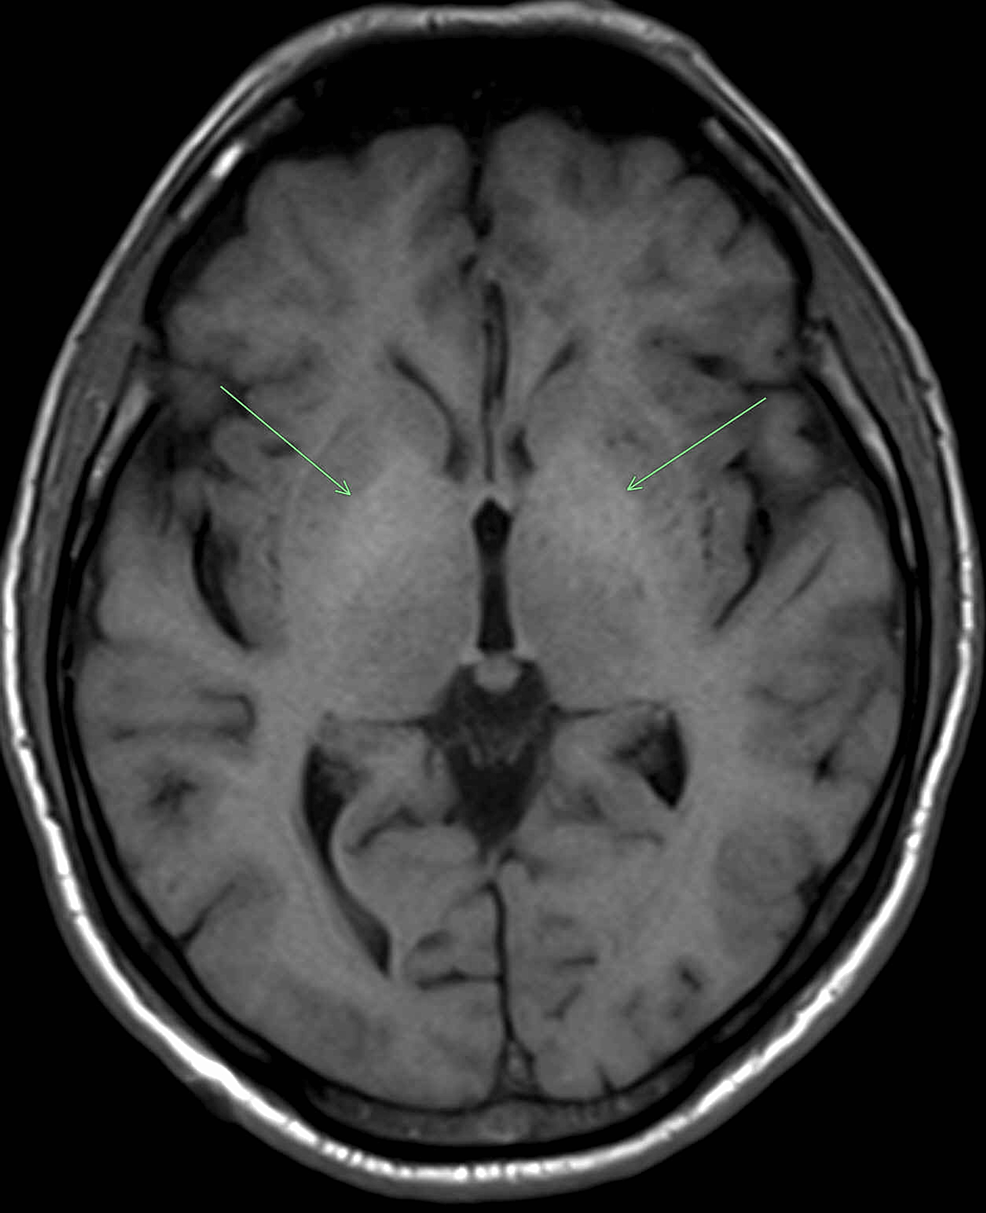

Figure.Hyperintensity over right basal ganglia on T1 weighted MRI

Basal Ganglia T1 Hyperintensity . various substances, including methemoglobin, melanin, lipid, protein, calcium, iron, copper, and manganese, are. basal ganglia and thalamus signal abnormalities occur in a wide variety of conditions. Hyperintense basal ganglia ( a ). a mri 2 days later demonstrates bilateral symmetric swelling and hyperintensity in the basal ganglia. t1 hyperintensity of the basal ganglia may be related to a minor hemorrhage resulting from rbc diapedesis after reperfusion.